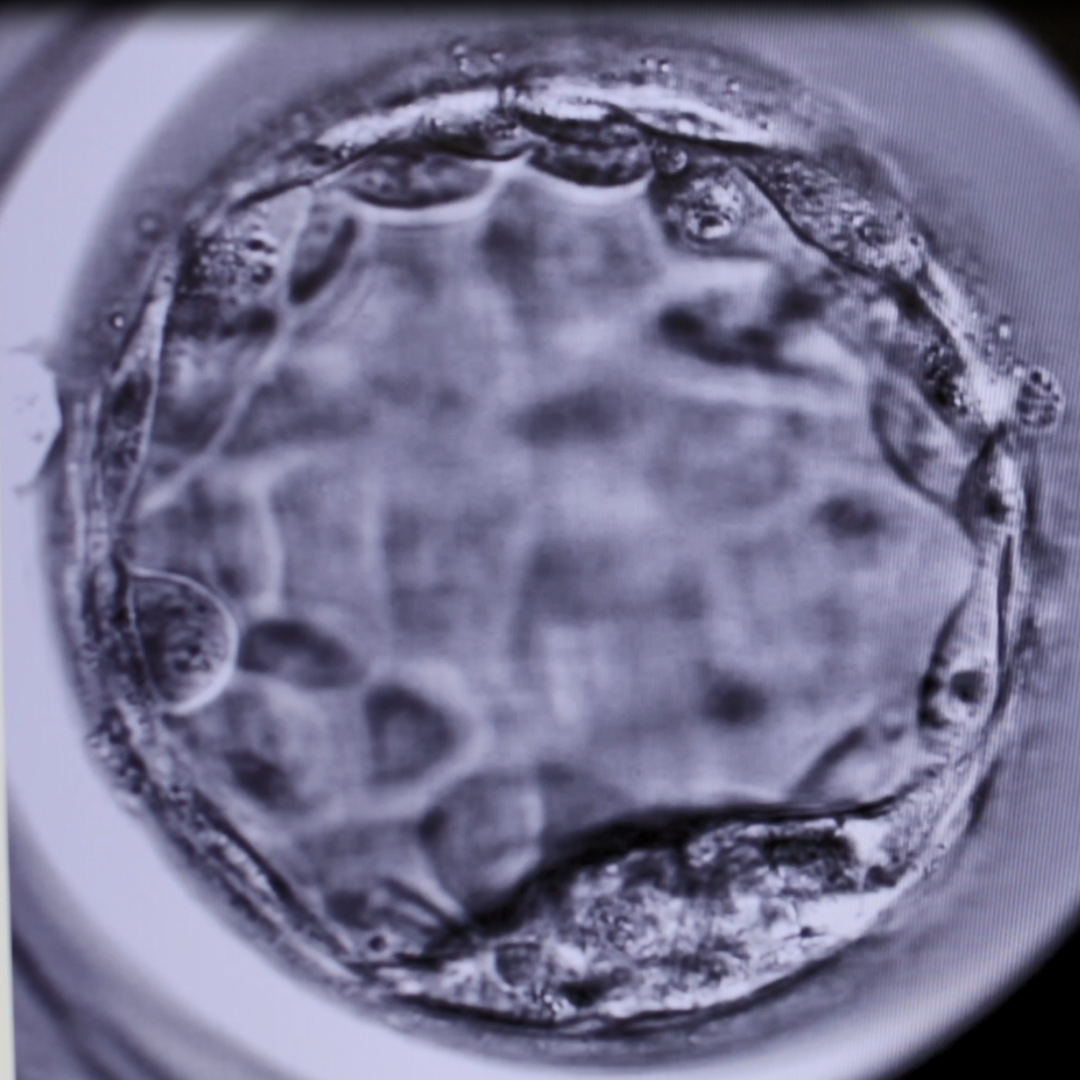

The IVF process involves the creation of multiple embryos during what is called a “stimulated cycle”. One embryo is usually placed into a uterus at its conclusion and many women also have excess embryos that are frozen for future use. In cases where pregnancy does not eventuate in the first round, frozen embryos can be used in subsequent months (this is termed a “thaw cycle”) without the need for ovarian stimulation and egg collections.

The embryo and endometrial lining must be synchronized in thaw cycles for successful implantation. There are a number of ways this synchronization can be achieved, and they can be divided into two broad groups – those that involve endogenous hormone production and those that do not.

Cycles that rely on external hormones are called “artificial thaw” and those that have natural hormone produced are called “natural” or “stimulated” thaw cycles.